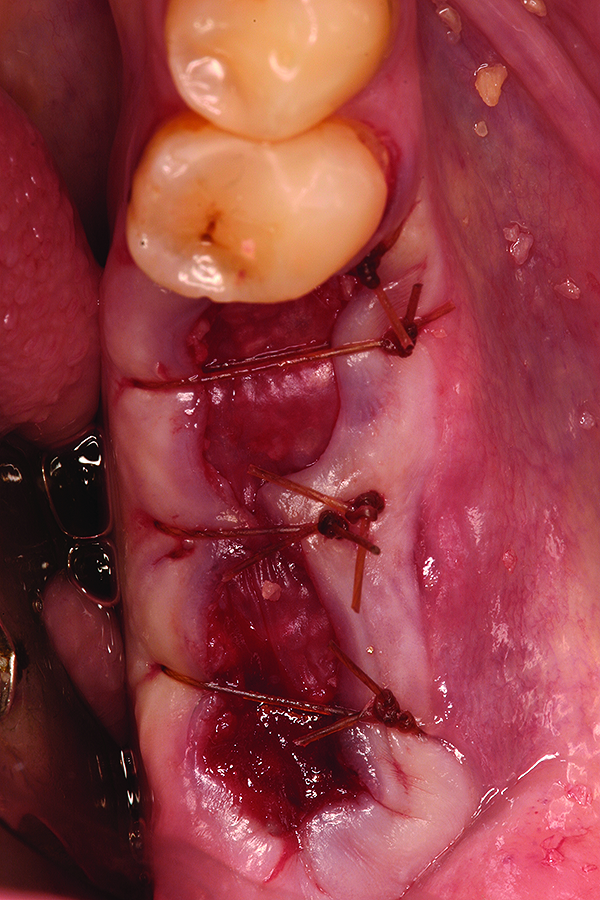

Fig 17. Placement of bone allograft into the extraction site.

Figure 17

Fig 18. Surgical site at 3 months healing.

Figure 18

Fig 19. Placement of dental implant into healed bone. Note complete circumferential bone surrounding all aspects of the dental implant.

Figure 19